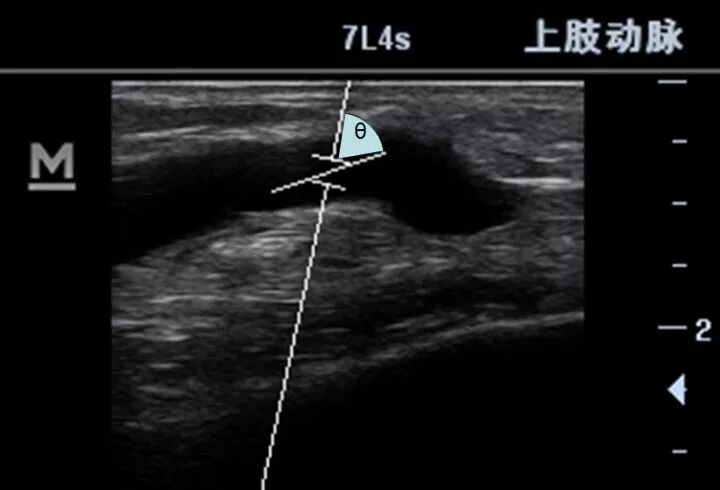

如下图所示,这就是多普勒角度θ。

什么是超声容积探头血流量测定 |取样容积和角度θ_https://www.jmylbn.com_新闻资讯_第6张

理论上,多普勒声束与血流完全同向时,测量的精度最好,这时的θ角为0度,然而,这种角度似乎只有血管内探头才可能实现。

体表探头与血管总是存在角度,直接测得的速度需要经过三角函数的矫正才能得到血流速度,而这个角度大于60度后,矫正的误差会很大,所以要求θ角应当小于60°。换句话说,就是探头要尽可能避免与血管垂直。而且这个角度越小,误差越小